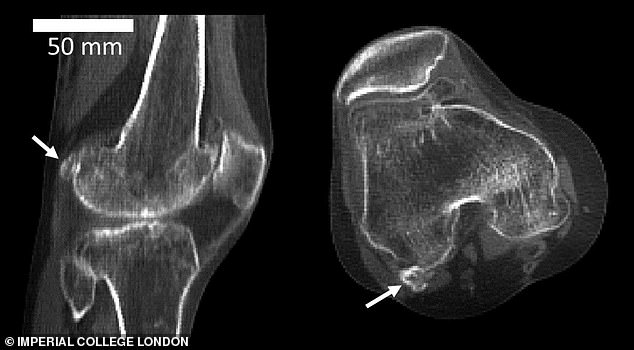

وأوضح العلماء، بحسب ما اوردت شبكة “إرم نيوز”، أن عظمة الفويلة قد تسبب الألم أيضًا بعد جراحة استبدال الركبة، حيث تبقى مكانها وتخترق عظمة الفخذ، وفقًا لصحيفة ”ديلي ميل“ البريطانية.

وبمقارنة العلماء لبيانات أكثر من 21 ألف دراسة أُجريت على مدى 150 عامًا، وجدوا أن 11.2 % من سكان العالم في عام 1918، كان لديهم عظمة الفويلة، ولكن تلك النسبة زادت وبلغت 39 % في العام الماضي.